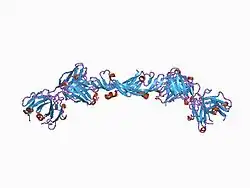

This gene is a member of the platelet-derived growth factor (PDGF)/vascular endothelial growth factor (VEGF) family and encodes a protein that is often found as a disulfide linked homodimer. This protein is a glycosylated mitogen that specifically acts on endothelial cells and has various effects, including mediating increased vascular permeability, inducing angiogenesis, vasculogenesis, and endothelial cell growth, promoting cell migration, and inhibiting apoptosis. Alternatively spliced transcript variants, encoding either freely secreted or cell-associated isoforms, have been characterized.[6]

Vascular endothelial growth factor A (VEGF-A) is a dimeric glycoprotein that plays a significant role in neurons and is considered to be the main, dominant inducer of the growth of blood vessels. VEGFA is essential for adults during organ remodeling and diseases that involve blood vessels, for example, in wound healing, tumor angiogenesis, diabetic retinopathy, and age-related macular degeneration. During early vertebrate development, vasculogenesis occurs which means that the endothelial condense into the blood vessels. The differentiation of endothelial cells is dependent upon the expression of VEGFA and if the expression is abolished then it can result in the death of the embryo. VEGFA is produced by a group of three major isoforms as a result of alternative splicing and if any three isoforms are produced (VEGFA120, VEGFA164, and VEGFA188) then this will not result in vessel defects and death of the full VEGFA knockout in mice. VEGFA is essential in the role of neurons because they too need vascular supply and abolishing the expression of VEGFA from neural progenitors will result in defects of the brain vascularization and neuronal apoptosis. Anti-VEGFA therapy can be used to treat patients with undesirable angiogenesis and vascular leakage in cancer and eye diseases but also could result in the inhibition of neurogenesis and neuroprotection. VEGFA could be used to treat patients with neurodegenerative and neuropathic conditions and also increase vascular permeability which will stop the blood-brain barrier and increase inflammatory cell infiltration.[7][8][9]